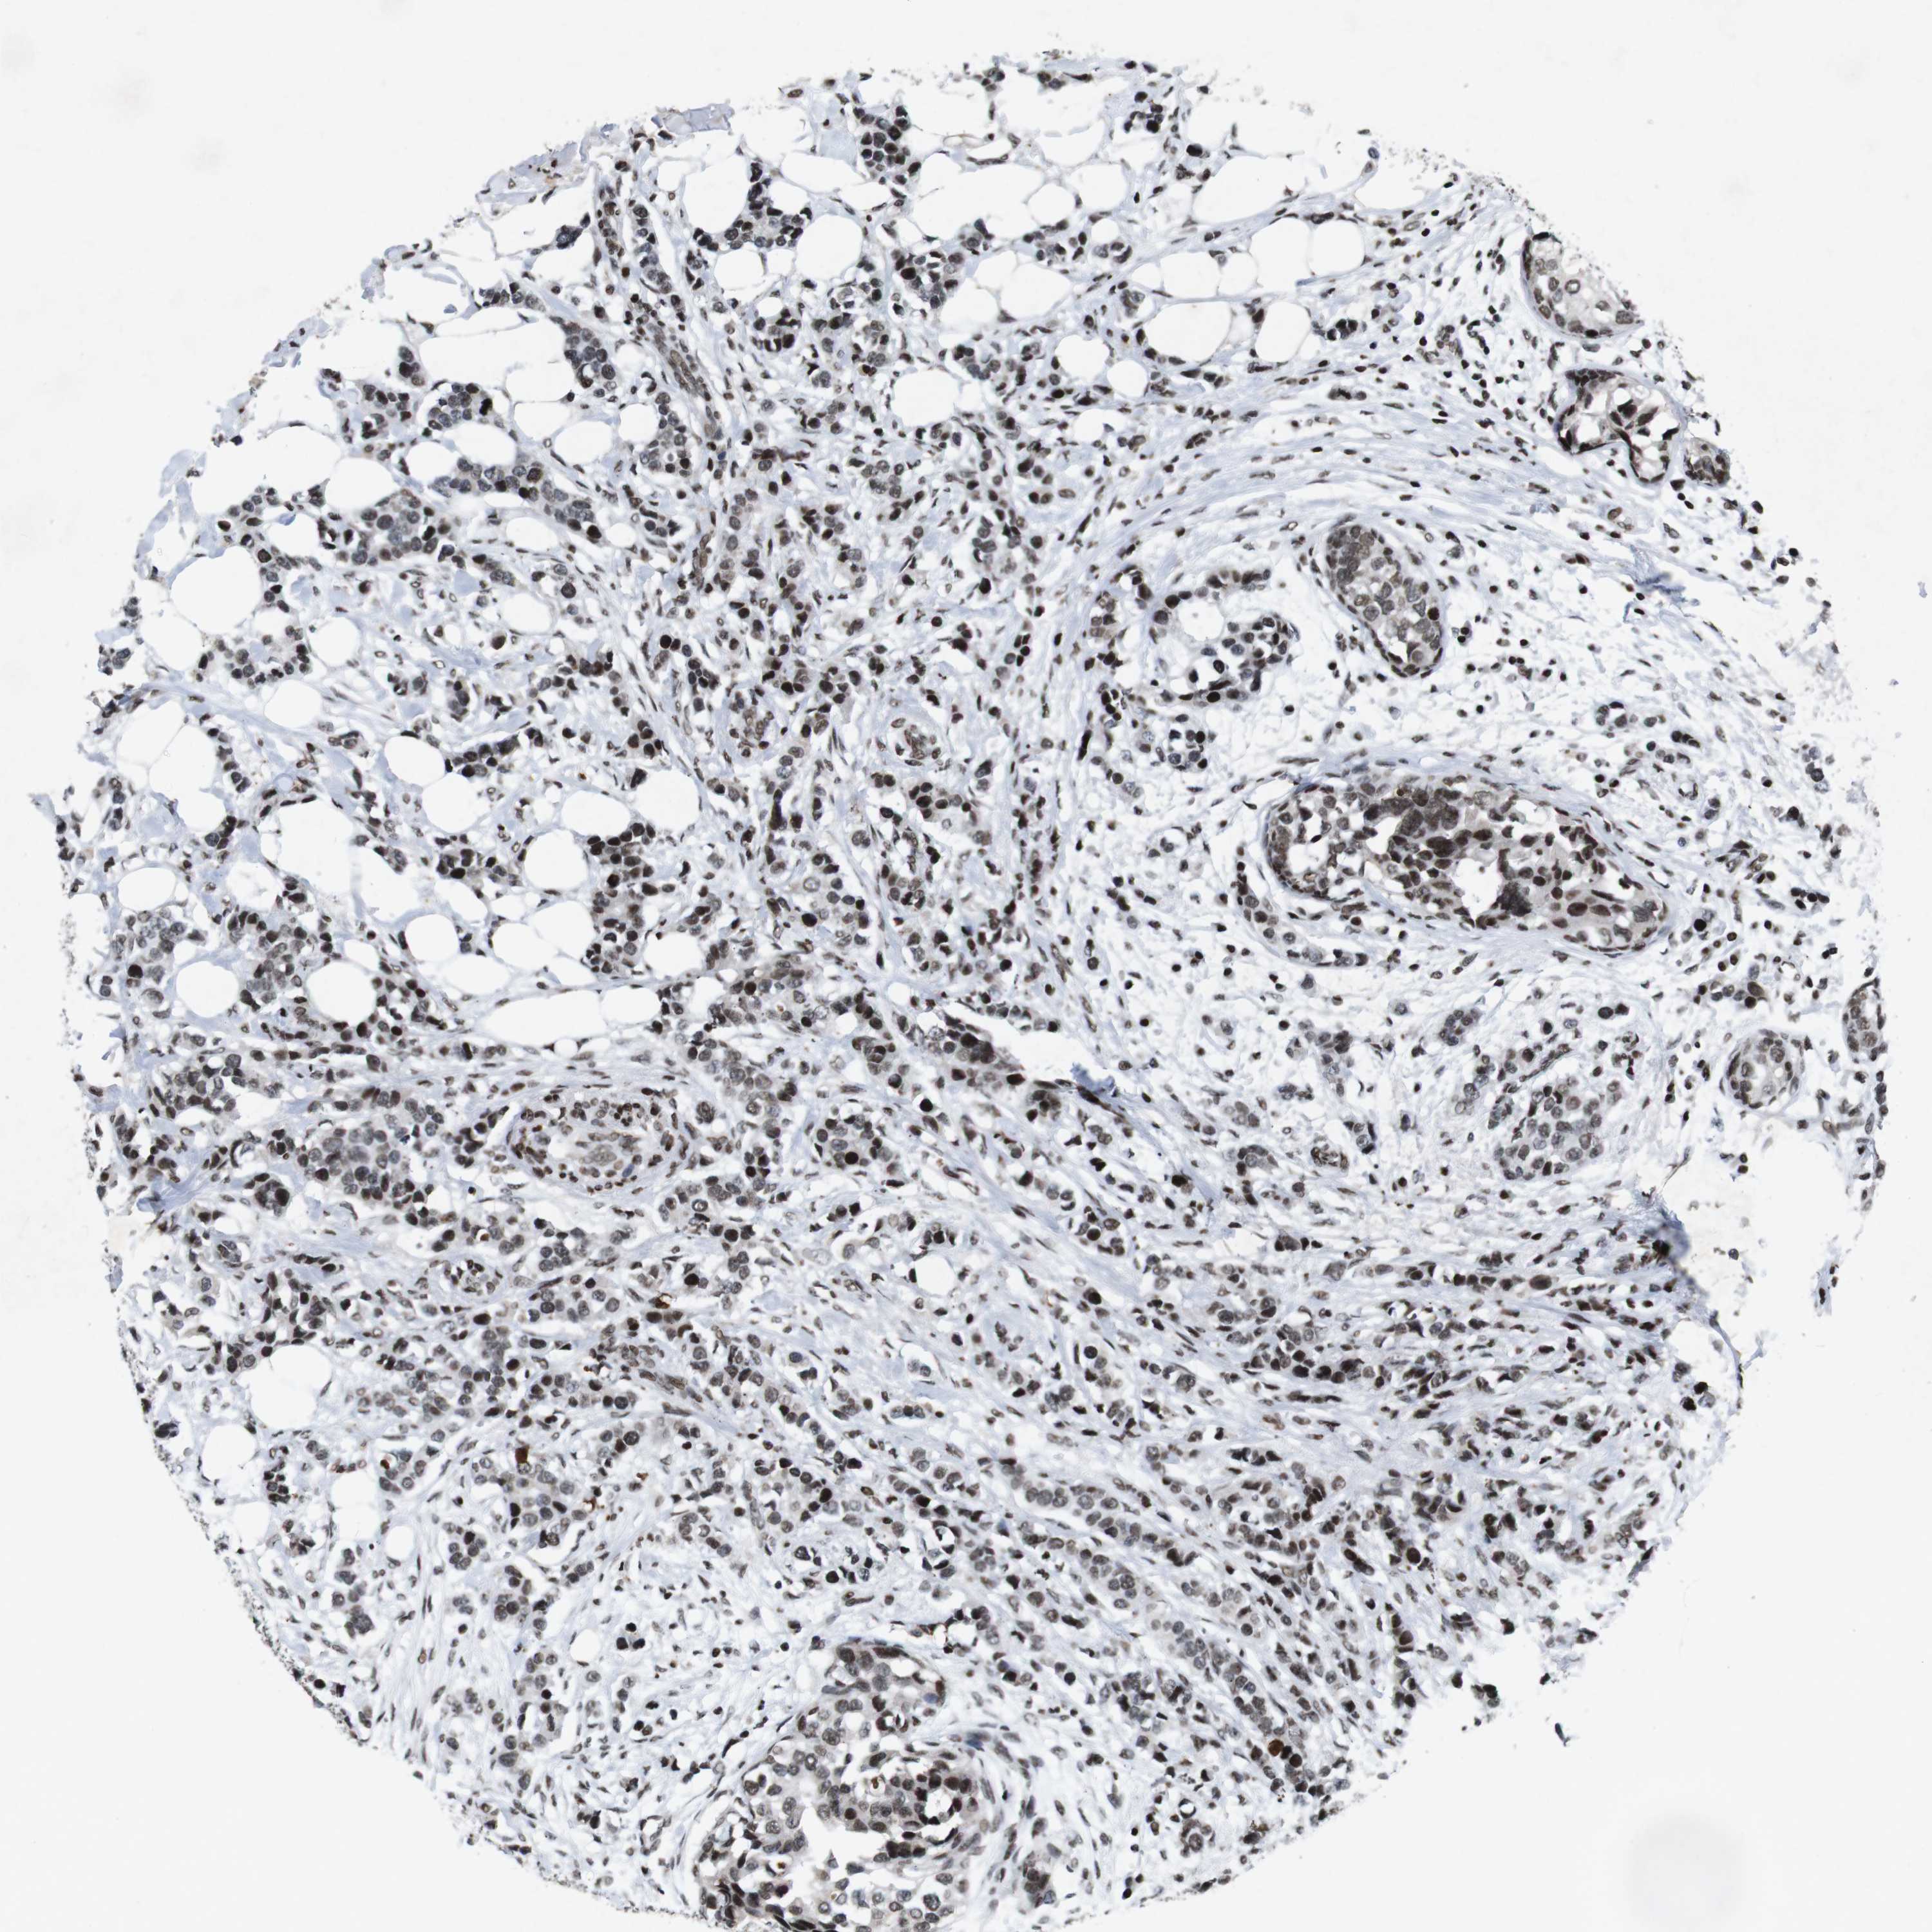

CANCER BREAST CANCER Show tissue menu

BRCA TCGA BRCA VALIDATION PROTEIN EXPRESSION